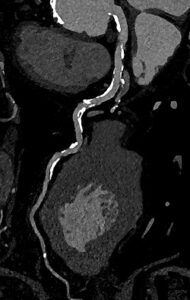

Erstmals nichtinvasive Diagnostik für Hochrisiko-Herzpatienten30. Juni 2023 Photon-Counting-CT des Herzens. Trotz sehr schwerer Verkalkungen an den Gefäßwänden (3D-Aufnahme), gelingt eine diagnostische Darstellung, die zeigt, dass die Gefäße nicht verstopft sind. Ein Herzkathetereingriff ist in diesem Fall nicht nötig. Bild: © Universitätsklinikum Freiburg Die ultrahochauflösende volldigitale Photon-Counting-Computertomographie ermöglicht bei Hochrisikopatientinnen und -patienten erstmals eine präzise nichtinvasive Untersuchung von Herzkrankheiten, das zeigt eine Studie im Fachmagazin „Radiology“. Ein Team des Universitätsklinikums Freiburg zeigt in einer aktuellen Studie, dass die neue Generation an Computertomographen, die sogenannten Photon-Counting-CTs, die Diagnose und Bildqualität bei einer Koronaren Herzerkrankung bei Hochrisikopatientinnen und -patienten deutlich verbessert. Dies könnte ein bedeutender Vorteil für Personen sein, bei denen bisher schnell ein invasiver Herzkatheter nötig war. „Unsere Ergebnisse zeigen, dass mit der neuen CT-Technologie deutlich mehr Patient:innen von einer nichtinvasiven CT-Untersuchung des Herzens profitieren als bisher“, sagt Prof. Fabian Bamberg, Ärztlicher Direktor der Klinik für Diagnostische und Interventionelle Radiologie des Universitätsklinikums Freiburg. „Das sind ausgezeichnete Neuigkeiten für diese Patient:innen und wird die klinische Versorgung weiter verbessern.“ Präzise Bilder als Grundlage für die Therapie Photon-Counting-CT-Aufnahme, die zeigt, dass die Gefäße nicht verstopft sind. Bild: ©Universitätsklinikum Freiburg Die koronare CT-Angiographie eignet sich besonders gut zum Ausschluss einer Koronaren Herzerkrankung bei Menschen mit niedrigem oder mittlerem Risiko für Veränderungen der Herzkranzgefäße. Bei Personen mit hohem Risiko gestaltete sich dies bislang aufgrund von häufig auftretenden koronaren Verkalkungen und Stents jedoch schwierig. Muhammad Taha Hagar, Erstautor der Studie und Arzt der Klinik für Diagnostische und Interventionelle Radiologie am Universitätsklinikum Freiburg erklärt: „In klassischen CT-Bildern erscheinen Verkalkungen der Herzkranzgefäße oft größer als sie tatsächlich sind. Dieser Effekt ist umso stärker, je größer die Verkalkung ist.“ Dadurch konnte es bislang zu einer Überbewertung von Verengungen und Plaques und in der Folge zu einer Überbehandlung kommen. Darum wurden diese Personen bislang schnell in den Herzkatheter überweisen oder in der Magnetresonanztomografie untersucht.“ In der von Hagar und Kolleginnen und Kollegen durchgeführten Studie wurden 68 Studienteilnehmende mittels Photon-Counting-CT und einer invasiven Koronarangiographie als Referenzstandard untersucht. Die Patientinnen und Patienten litten alle unter einer schweren Aortenklappenstenose, einer gängigen, aber ernsthaften Herzerkrankung, die den Blutfluss vom Herzen zur Aorta reduziert oder blockiert. Die Photon-Counting-CT-Untersuchung zeigte sich sehr genau in der Erkennung oder dem Ausschluss der Koronaren Herzerkrankung. Auch wurde die Bildqualität in fast 80 Prozent als gut oder hervorragend bewertet. Das Photon-Counting-CT ist deutlich sensibler als klassische CT-Geräte und benötigt eigentlich weniger Strahlung für vergleichbare Bilder. Um die in der Studie erreichte Bildqualität zu erhalten, war jedoch eine etwas höhere Strahlenexposition als bei klassischen CT-Verfahren notwendig. Darum ist die Methode zunächst vor allem für Personen mit hohem Risiko geeignet, die von den hochauflösenden Bildern besonders profitieren. Starke Verbreitung der Technologie erwartet Noch sind Photon-Counting-CT-Geräte wie das am Universitätsklinikum Freiburg weltweit relativ selten, doch Expertinnen und Experten rechnen damit, dass diese Technologie in den nächsten zehn Jahren zunehmend Verbreitung finden und die CT-Diagnostik maßgeblich verändern wird. Beim „Photon-Counting“ entsteht durch die hochauflösende direkte Umwandlung der eintreffenden Photonen ein digitales Signal, welches direkt auswertbar ist. Die Methode gilt damit als Grundlage für eine substantiell verbesserte digitale Patientenversorgung und für eine Nutzung der generierten Daten für zukünftige Therapieansätze. Das Forschungsteam untersucht nun das diagnostische Potenzial der photonenzählenden CT-Technologie in anderen klinischen Szenarien, wie beispielsweise in der Onkologie. Weiterhin möchte es seine Studien auf Untergruppen erweitern, für die eine CT-Bildgebung derzeit nicht realisierbar ist, beispielsweise Patientinnen und Patienten mit koronaren Stents oder die Beurteilung des Herzmuskels mit dem Photon-Counting-CT.